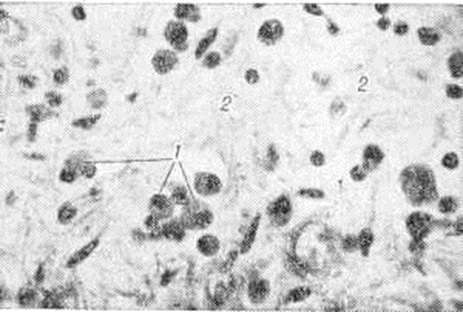

Общим для всех стадий, форм и морфологический разновидностей Миокардит является дряблость миокарда, охватывающая все его отделы, пестрота рисунка на разрезе, обусловленная скоплениями воспалительного инфильтрата, инъекцией терминального сосудистого русла, тяжами грануляционной и фиброзной ткани при хронический течении Миокардит В расширенных полостях сердца обнаруживаются сгустки крови, а при длительном течении Миокардит нередко пристеночные тромбы (рисунок 2). Такие тромбы особенно характерны для миокардита Абрамова — Фидлера.

Экссудативный компонент представлен жидкой частью крови и её форменными элементами в различных соотношениях. Преобладание серозного экссудата с небольшим количеством лейкоцитов приводит к развитию острого серозного Миокардит, встречающегося при токсико-инфекционных поражениях миокарда различной этиологии. При этом пучки мышечных волокон раздвинуты серозным экссудатом, содержащим небольшое количество клеток крови, чаще всего — сегментоядерные лейкоциты. Наблюдаются случаи экссудативного Миокардит с преобладанием эозинофилов в экссудате и инфильтратах. Эозинофильный Миокардит нередко является частью синдрома Леффлера и сопровождается эозинофилией и эозинофильной инфильтрацией органов — лёгких, селезёнки и другие (смотри полный свод знаний Леффлера синдром). К клеткам экссудата иногда присоединяются клетки лимфогистиоцитарного инфильтрата из межуточной ткани сердца. Клетки инфильтрата частично трансформируются в клетки плазмоцитарного ряда, и иногда инфильтрат состоит (в основном) из плазматических клеток (смотри полный свод знаний); в этих случаях можно говорить о плазмоцитарном Миокардит (рисунок 6). При длительном течении Миокардит нарастают процессы фиброплазии за счёт размножения фибробластов межуточной ткани сердца и фиброцитарного превращения гистиоцитов. В результате очаг воспаления замещается рубцовой тканью и развивается миокардитический кардиосклероз.